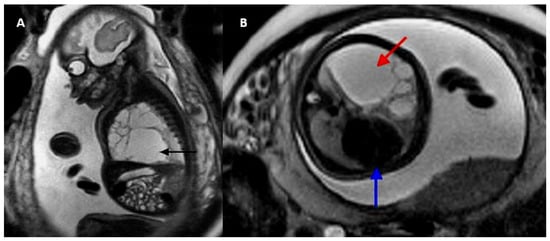

3. Diagnosis and Classification

Early detection is essential for prenatal and postnatal follow-up and is directly related to lesion size, degree of mediastinal deviation, fetal hemodynamics, and associated anomalies [5]. Prenatal diagnosis of CCAM is based on ultrasound findings (Table 1), most commonly detected in the second trimester of pregnancy and classified into three subtypes according to Stocker [5,6] (Table 2 and Figure 1). Although magnetic resonance imaging (MRI) has high sensitivity and specificity for detecting lung lesions, it has not been shown to add diagnostic or prognostic value over ultrasound [4] (Figure 2).

Figure 1. Two-dimensional ultrasonography. Classification congenital adenomatoid cystic malformation. (A) Subtype I, (B) Subtype II, and (C) Subtype III. Source: the authors.